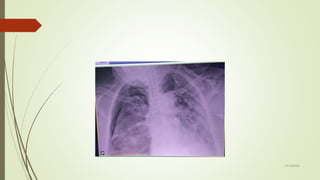

VAMOS

TREINAR?????